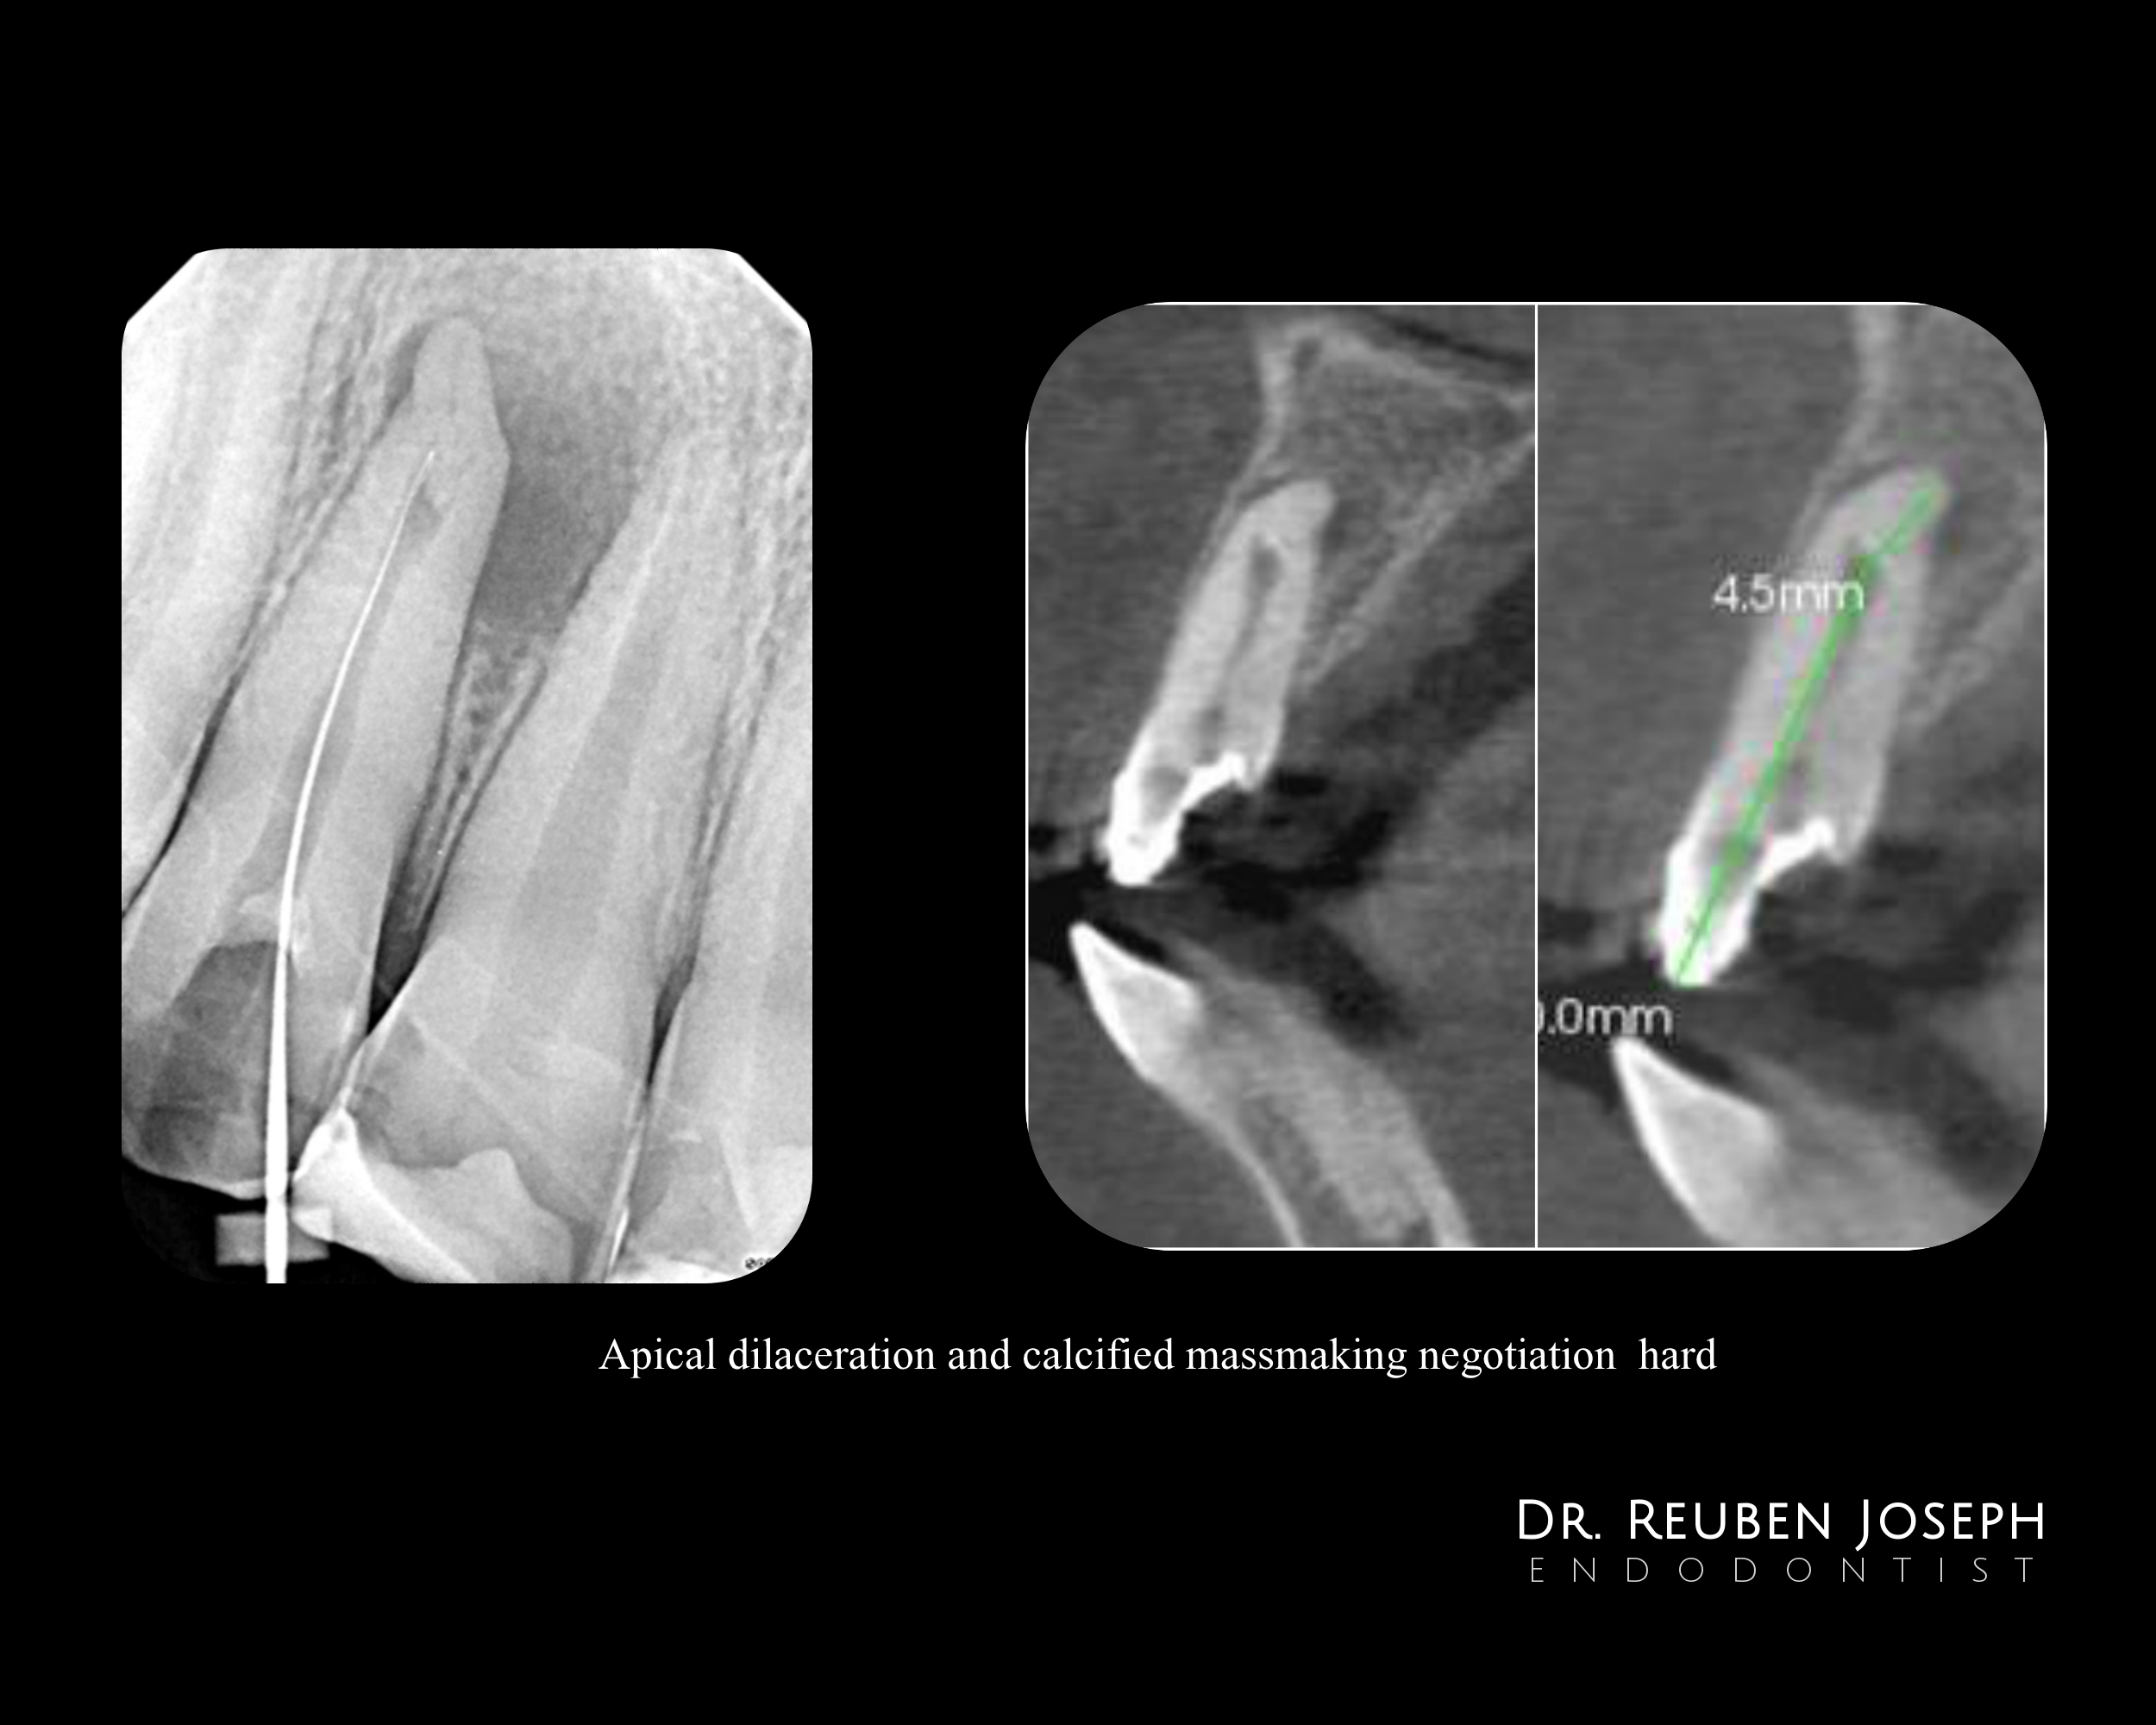

> CBCT findings

No communication of internal resorption externally.

A sharp palatal curve of the root apically.

– Unable to establish patency to length due to the calcified mass within the internal resorption and CBCT recommended.

– Calcification drilled out and canals shaped and CaOH dressing (1st visit)